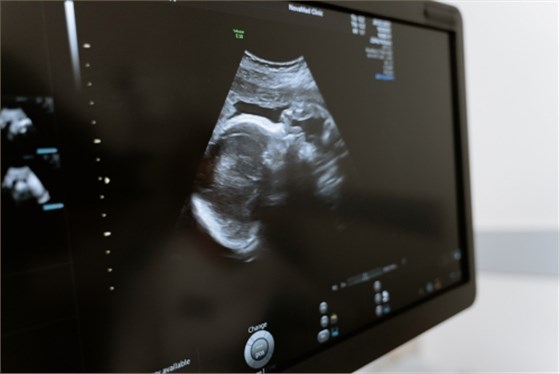

常規超聲檢查指的是二維超聲檢查,二維超聲檢查即二維超聲檢查,小排畸是為了更好地觀察胎兒生長發育情況,排除畸形的檢查。小排畸檢查能夠排除絕大多數胎兒畸形,如先天性心臟病、唇腭裂、水腫胎,以及多指畸形、重度腦膨出等。

1、先天性心臟病:可通過二維超聲檢查直接觀察心臟及大血管的形態、結構、連續性及血流改變,二維超聲檢查比較直觀,能夠顯示出心臟的三維圖像,所以在懷孕期間需要定期做產檢,一般在懷孕20-26周需要做四維彩超大排畸檢查,判斷胎兒是否有畸形;

2、唇腭裂:二維超聲檢查能夠比較清晰地顯示出胎兒嘴唇及面部發育情況,而且還能夠觀察到是否存在唇腭裂的情況,所以在懷孕期間需要常規做三維彩超檢查,判斷胎兒是否存在唇腭裂;

3、水腫胎:如果孕婦出現水腫胎,也需要做二維超聲檢查,判斷胎兒是否存在水腫胎,因為如果孕婦出現水腫胎,大多是由于妊娠期高血壓導致,所以在懷孕期間要定期做產檢,隨時觀察水腫胎的情況;

4、多指畸形:產前二維超聲檢查可以觀察到胎兒手指、腳趾等外觀畸形,如果出現多指畸形,還需要做三維超聲檢查,判斷是否有多指畸形的情況;

5、重度腦膨出:二維超聲檢查能夠比較清晰地觀察胎兒腦組織、脊柱、羊水等情況,如果出現重度腦膨出,也需要做三維超聲檢查判斷是否有腦積水。

孕期需要做好定期產檢,建議在懷孕24-26周需要到醫院做四維彩超大排畸檢查,判斷胎兒是否有畸形,如果出現比較嚴重的畸形,建議在醫生指導下終止妊娠。